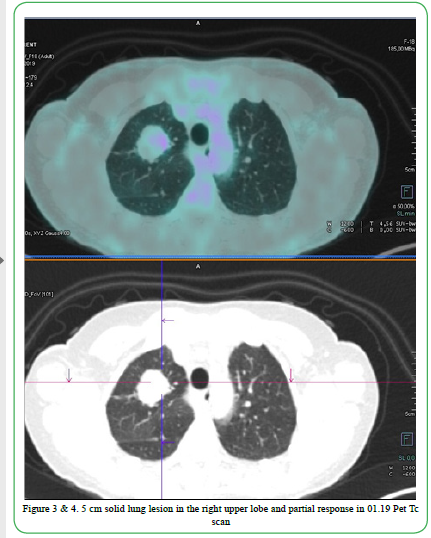

The treatment went on for 3 months with good tolerance and no relevant toxicities in patient reported outcomes. Not hematologic toxicities were described too. After only 2-3 weeks of treatment patient revealed an impressive cough improvement maintaining an optimal quality of life. The 18 FDG Pet- CT scan performed in January 2019, after three months of treatment showed a complete radiological response on spleen, left iliac bone, liver and D3, and a partial response (RECIST criteria) on pulmonary lesion. Cough completely disappeared and no toxicities appeared during the first three months treatment with Alectinib full dose.

Figure 3 & 4. 5cm solid lung lesion in the right upper lobe and partial response in 01.19 Pet Tc scan